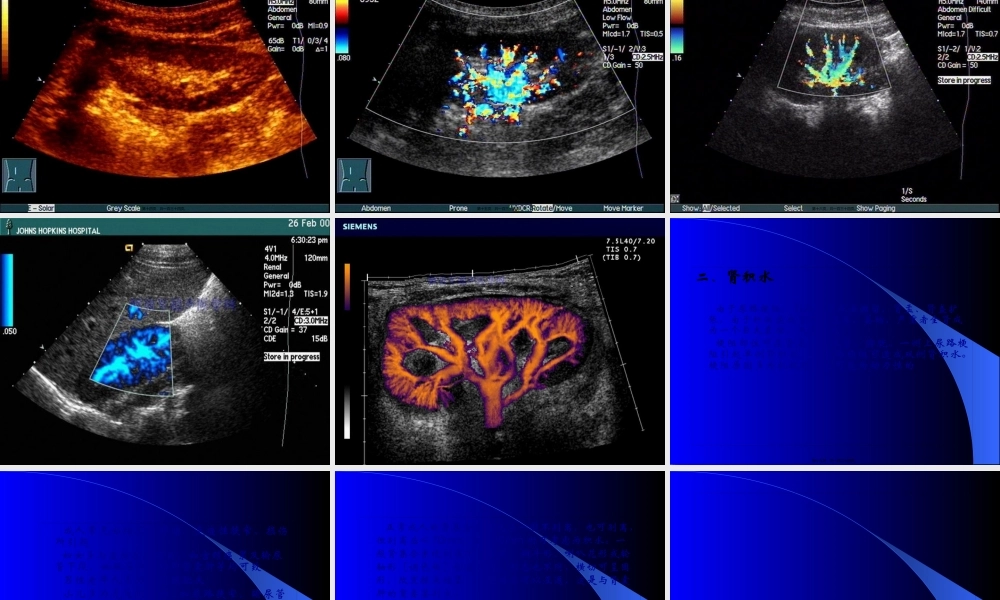

泌尿系统的超声诊断ClicktoaddText第一页,共一百三十四页。适应范围一、对肾、输尿管、膀胱、肾上腺、前列腺的占位性病变是首选二、尿路结石三、泌尿系先天畸形四、膀胱异物五、肾损伤〔挫伤、裂伤〕六、肾感染:脓肿、结核、尿毒症、肾纤维化七、胡桃夹综合征八、移植肾第二页,共一百三十四页。正常成人肾大小:长度10-12cm,宽5-7cm,厚3-5cm,男略大于女。肾的凹陷处为肾门,是肾静脉,肾动脉,肾盂出入肾处〔肾静脉在前,肾动脉居中,最后是肾盂〕第三页,共一百三十四页。•肾脏是人体主要器官之一,是一对很象蚕豆形的内脏。它在腹后腔的脊柱两旁各一个。正常男性每个肾重约120—170克,相当于本人握起的拳头大小,女性较男性稍小。第四页,共一百三十四页。肾脏分实质和肾窦,肾实质又分皮质和髓质,皮质厚5—7mm。肾小球就在皮质,皮质伸入肾椎体之间的局部为肾柱,髓质由8—15个肾椎体组成,肾椎体的尖端是肾乳头,伸到肾窦的肾小盏中,肾小盏8—12个,集合成2—3个肾大盏→肾盂。肾窦由肾盏、肾盂、肾动脉、静脉和脂肪等组织所组成,超声也称集合系统。第五页,共一百三十四页。膀胱是一肌性囊状贮尿器官,尿液充盈时近似椭圆形。膀胱的后下方为三角区,为两侧输尿管的出口和尿道内口,膀胱前方男性为前列腺,女性为子宫第六页,共一百三十四页。第七页,共一百三十四页。第八页,共一百三十四页。第九页,共一百三十四页。第十页,共一百三十四页。2.正常声像图:(1)肾脏冠状切面呈豆形,俯卧位呈椭圆形,肾脏的轮廓线明显光滑,肾皮质为细小均匀的低回声光点,肾椎体为圆锥形,呈放射状排列弱回声区,肾窦又称集合系统,是肾盂、肾盏、血管和脂肪的回声,为密集增强的光点回声,宽度约占肾前后径1/2—1/3。含尿液时,中央可出现暗区直径小于1厘米第十一页,共一百三十四页。(2)输尿管在不扩张时,图象上不显示(3)膀胱壁光滑、连续、充盈膀胱时壁厚约1mm,排尿后厚约3mm(4)前列腺大小:3×4×2cm,呈粟形,内光点分布均匀第十二页,共一百三十四页。第十三页,共一百三十四页。第十四页,共一百三十四页。第十五页,共一百三十四页。第十六页,共一百三十四页。第十七页,共一百三十四页。第十八页,共一百三十四页。二、肾积水由于尿路梗阻,引起肾内尿液潴留,肾盂、肾盏扩张,由于积液造成肾实质变薄、萎缩,严重者全肾成为一个巨大囊腔,失去功能梗阻部位可在肾盂、输尿管、膀胱。一侧上尿路梗阻引起单侧肾积水,下尿路梗阻可造成...

蜗牛文库的最新文档

二年级数学下册其中检测卷二年级数学下册其中检测卷附答案#期中测试卷.pdf